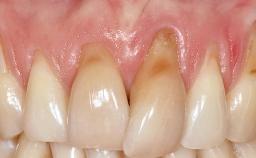

Early Implant Placement, Contour Augmentation, and Autologous Connective-Tissue Graft Using a Tunneling Technique to Replace an Upper Incisor with Generalized Gingival Recession

Variations in soft-tissue volume, evidenced either by an overabundance (Evian and coworkers 1993; Levine and McGuire1997; Dolt and Robbins 1997) or by a deficiency of soft or hard tissue can complicate implant-supported rehabilitations in the esthetic zone (Lorenzana 2008; Lorenzana and coworkers 2009). The present case illustrates the replacement of a failing upper left lateral incisor complicated by generalized severe gingival recession in the esthetic zone.

| Soft Tissue Anatomy | Intact | Defective | |

| Soft Tissue Contour and Volume | Significantly deficient |